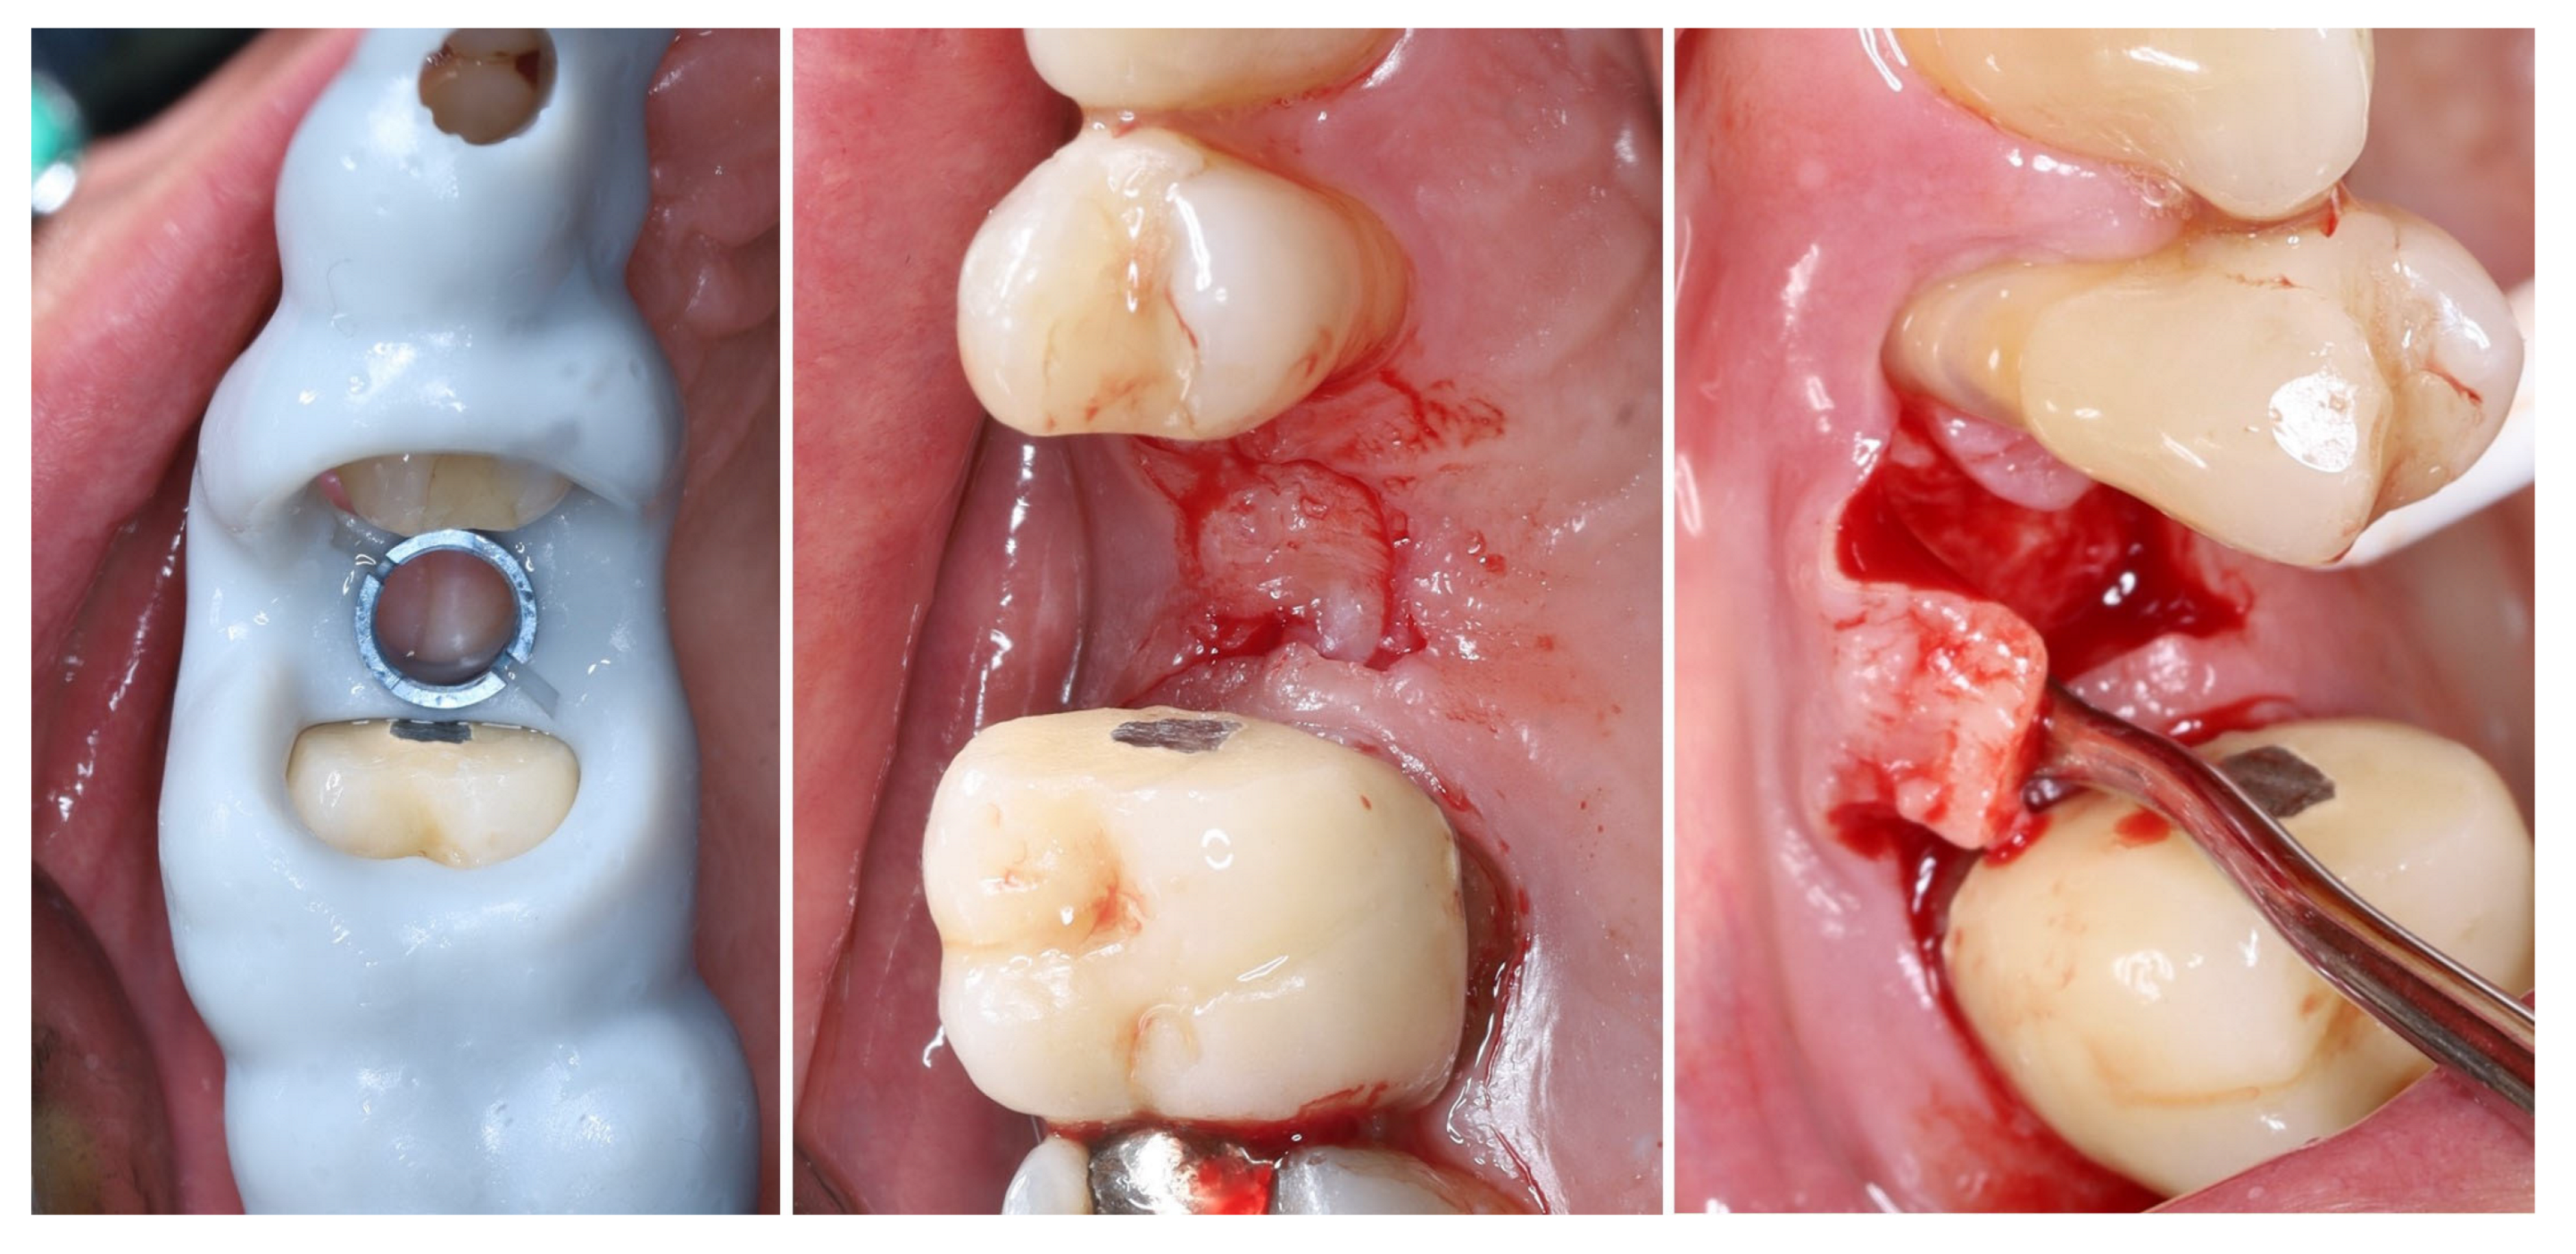

The selected implant was positioned in the prosthetically driven position, with appropriate bone thickness at the buccal aspect and surrounded by healthy soft tissues (left). Another advantage of this surgical approach is the possibility to adapt the implant insertion depth corresponding to the soft tissue thickness in order to provide enough soft tissue thickness to enhance the stability of the peri-implant bone. The intraoperative measurements confirmed excellent primary stability, with ISQ values of 82 bucco-lingually and 85 mesio-distally (right). These parameters indicated optimal mechanical anchorage of the fixture within the alveolar bone, ensuring favourable conditions for osseointegration (Figure 9).

Figure 9.

Implant placement and initial stability.

A multi-purpose healing abutment, serving also as a scan body (encode abutment ZimVie Inc., Palm Beach Gardens, FL, USA), was connected, providing proper concave emergence profile in the critical contour zone of the transmucosal area. The de-epithelized crestal flap was rolled and fixated to the inner surface of the buccal flap with a horizontal mattress suture (7/0 PGA). The buccal flap was fixed to the “anatomical” part of the peri-implant papillae (6/0 PGA). The buccal positioning of the rolled connective tissue creates a thickened gingival margin, intended to improve peri-implant soft tissue stability and long-term esthetic outcomes. The surgical site shows adequate adaptation of the flap margins around the healing abutment, enhancing the primary healing, thus reflecting proper flap management and atraumatic technique. The 2D X-ray performed after implant placement shows a proper implant position corresponding to the morphology of the alveolar crest (Figure 10).

Figure 10.

Clinical and X-ray view after implant placement and roll flap adaptation.